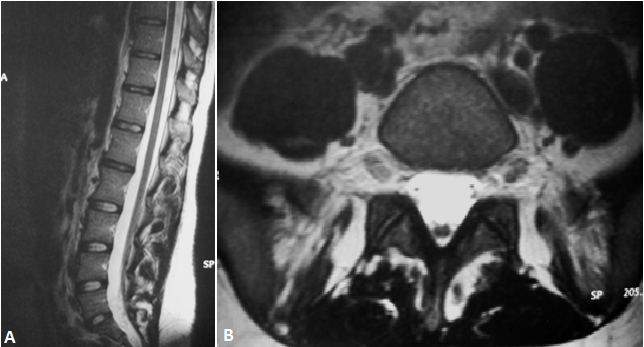

Le syndrome de la moelle bas attachée est une complication du dysraphisme spinal. Affection est souvent découverte chez l'enfant, peut être asymptomatique et rencontrée chez l'adulte. Nous rapportons le cas d'une jeune fille de 20 ans qui consultait pour une symptomatologie urinaire faite d'une dysurie et d'une impériosité mictionnelle évoluant depuis 2 mois. L'échographie rénovésicale ne montrait pas de lésion spécifique en dehors d'un résidu post mictionnel estimé à 80cc. Le bilan biologique était sans particularité. La cystomanométrie objectivait une vessie hyperactive. Une IRM du rachis lombaire a révélé un cône terminal en position basse au-dessous de L5 (A) avec un cordon médullaire de signal homogène en situation postérieure (B). Une intervention chirurgicale a permet une amélioration du retentissement urinaire. Au cours de cette affection, le niveau du cône médullaire se trouve en dessous du niveau L1-L2, et souvent associé à des malformations congénitales à type de filum épais ou de tumeurs bénignes. Les examens urodynamiques ont une place dans le diagnostic et dans le suivi des syndromes de moelle fixée. L'IRM est l'examen de choix pour confirmer le diagnostic et établir un bilan complet et précis. Le traitement est essentiellement chirurgical.